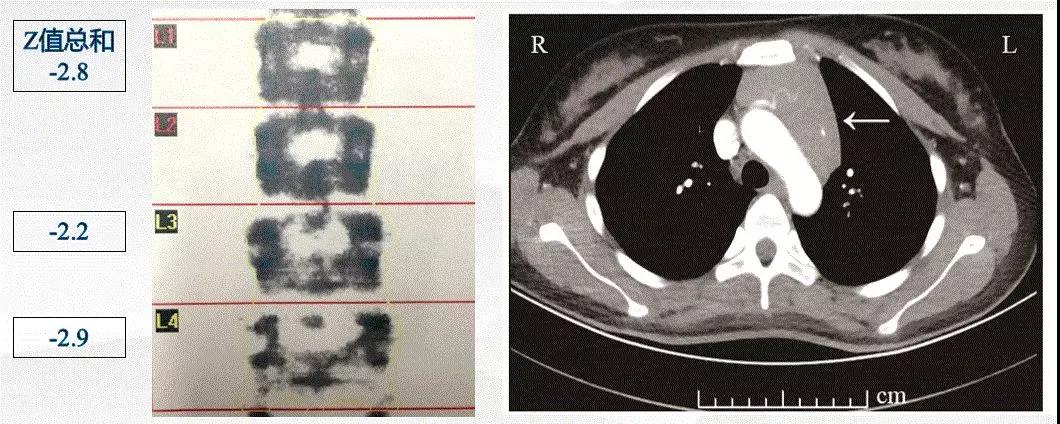

但在检查过程中,发现了两个明显异常的检查结果:严重骨质疏松和胸腺明显增大。因为患者年龄仅22岁,所以目前的骨密度对于患者来说是相当低的,部分骨代谢指标检测结果如下:骨钙素 51.46 ng/mL 增高(正常范围 11~46);B-胶原特殊序列 (βCTX) 2105.00 ng/L 增高(正常范围 < 573)此外,根据胸部CT图像,我们初步计算了胸腺的体积,根据相应的公式,胸腺体积达到 1963.58 mm2。相应结果如下:

微信图片_20210315141636.jpg

患者甲亢治疗8个月后,患者骨密度有改善,L1-4骨密度-2.4g/cm2,颈部骨密度-0.7g/cm2。让我们意外欣喜的是,患者复查胸部CT显示明显肿大的胸腺已经明显缩小,经过公式计算,胸腺体积已经缩小至 911.01 mm2,治疗前后的CT结果比较如下:

微信图片_20210315141844.png